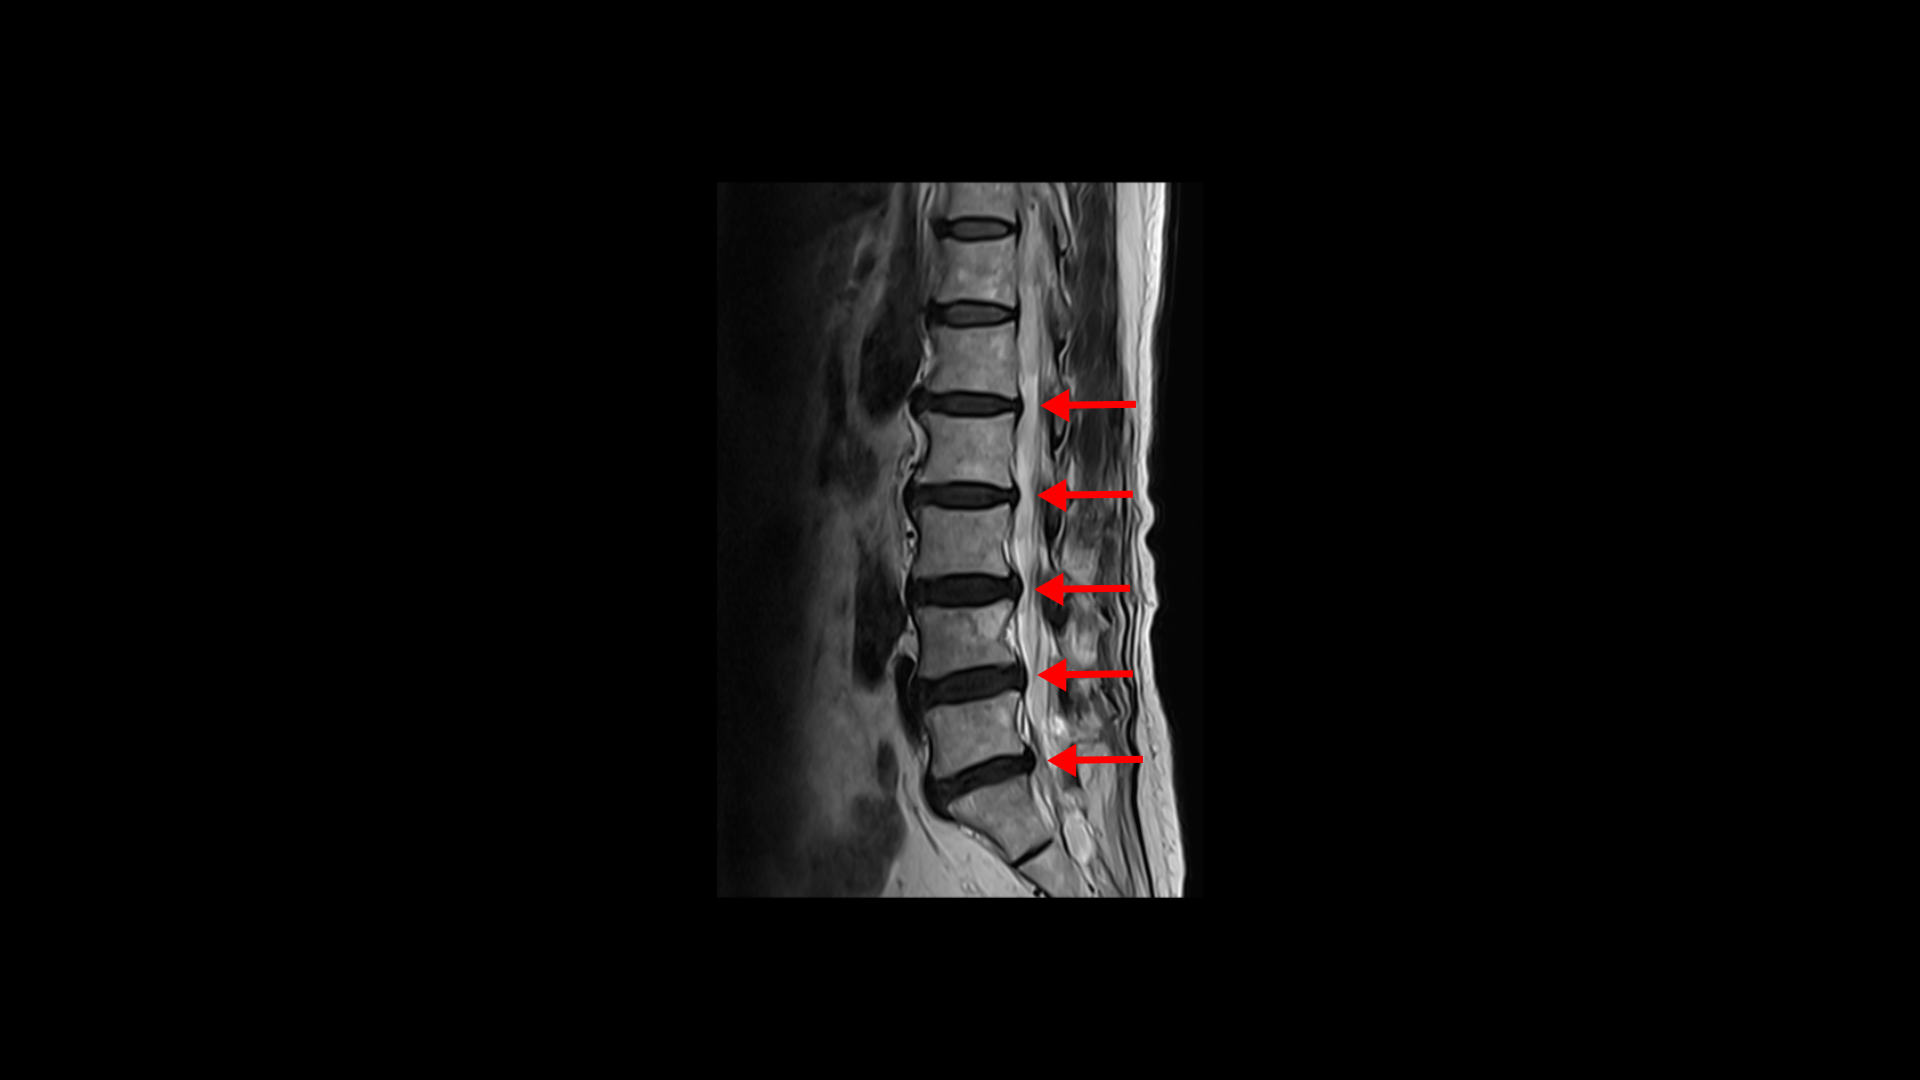

이분 MRI를 보면 74세의 연세답게 여러 마디의 퇴행성 디스크가 있습니다. 하지만 심하지 않습니다.

3번 4번에 황색 인대가 조금 두꺼워진 중심성 협착이 보이지만 역시 심하지는 않습니다.

좌우의 신경구멍도 막힌 곳이 없습니다.

그런데 이런 환자분들 중 협착이 조금이라도 보이니까 협착증 환자로 오진되어 협착증 치료만 받고 계신 분들도 많습니다.

역시나 어떤 척추병원에서는 협착증이라고 하면서 신경 주사를 허리에 여러 번 놓았지만 전혀 효과가 없었습니다. 대부분의 정형외과와 대학병원에서는 신경을 건드리는 게 없다, 손댈 게 없다며 주사도 안 놔줍니다. 한 척추전문병원에서는 정 답답하면 나사 박는 수술을 하는 수밖에 없다고 하였고, 대학병원에서는 그냥 참고 사시는 수밖에 없다고 들으셨습니다. 대학병원에서도 정 원하시면 나사박는 수술을 해드릴 수는 있는데 그러면 수술 후에 더 안 좋을 거라고, 안 하시는 게 좋다고 얘기했다고 합니다.